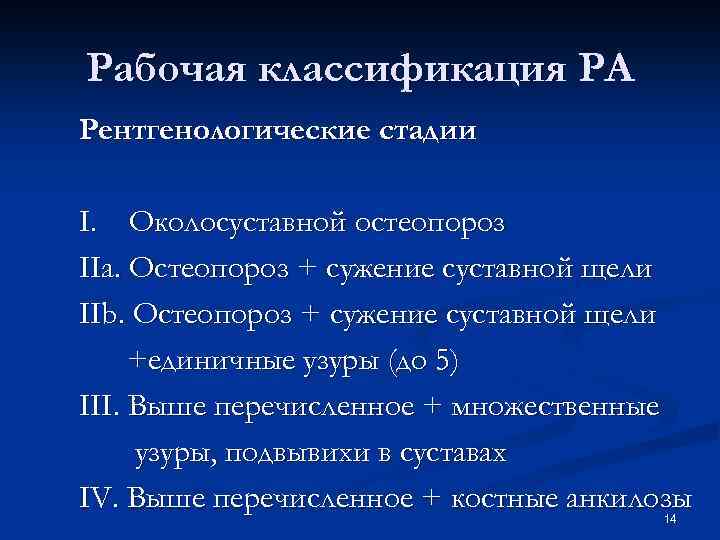

Рабочая классификация РА Рентгенологические стадии I. Околосуставной остеопороз IIa. Остеопороз + сужение суставной щели IIb. Остеопороз + сужение суставной щели +единичные узуры (до 5) III. Выше перечисленное + множественные узуры, подвывихи в суставах IV. Выше перечисленное + костные анкилозы 14

Рабочая классификация РА Рентгенологические стадии I. Околосуставной остеопороз IIa. Остеопороз + сужение суставной щели IIb. Остеопороз + сужение суставной щели +единичные узуры (до 5) III. Выше перечисленное + множественные узуры, подвывихи в суставах IV. Выше перечисленное + костные анкилозы 14